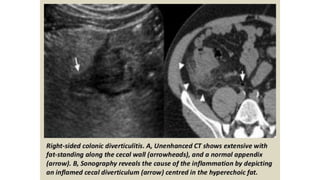

This document discusses the evaluation of right lower abdominal pain and lists appendicitis as a key cause. It notes that other potential causes include hemorrhagic cysts, heterotrophic pregnancy, salpingitis with pyosalpinx, funiculitis, and torsion of an undescended testis. The document was presented by Dr. A.S.M. Sufian of Cumilla Medical College Hospital and thanks the audience for their patience and listening.